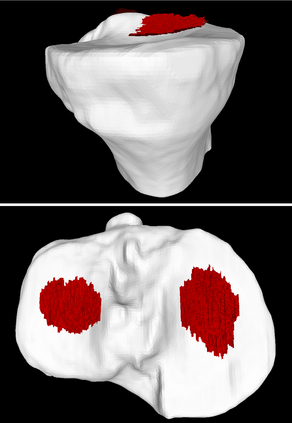

Analyzing knee cartilage thickness and strain under load can help to further the understanding of the effects of diseases like Osteoarthritis. A precise segmentation of the cartilage is a necessary prerequisite for this analysis. This segmentation task has mainly been addressed in Magnetic Resonance Imaging, and was rarely investigated on contrast-enhanced Computed Tomography, where contrast agent visualizes the border between femoral and tibial cartilage. To overcome the main drawback of manual segmentation, namely its high time investment, we propose to use a 3D Convolutional Neural Network for this task. The presented architecture consists of a V-Net with SeLu activation, and a Tversky loss function. Due to the high imbalance between very few cartilage pixels and many background pixels, a high false positive rate is to be expected. To reduce this rate, the two largest segmented point clouds are extracted using a connected component analysis, since they most likely represent the medial and lateral tibial cartilage surfaces. The resulting segmentations are compared to manual segmentations, and achieve on average a recall of 0.69, which confirms the feasibility of this approach.